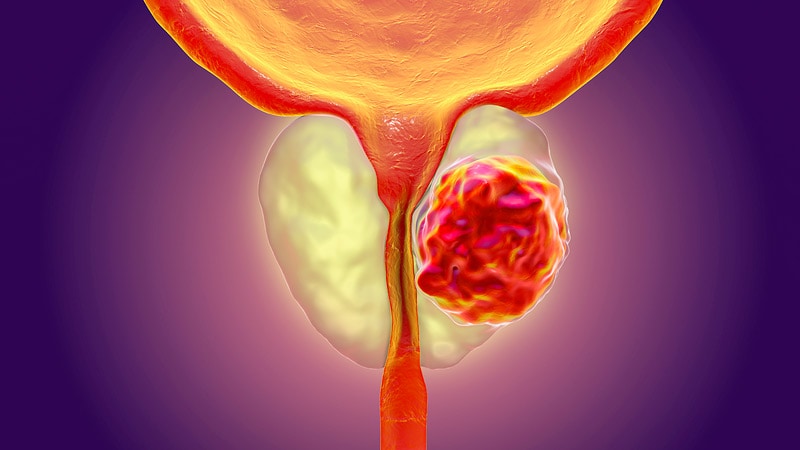

مقدمه بزرگ شدن پروستات که به عنوان هیپرپلازی خوشخیم پروستات (BPH) شناخته میشود، یکی از شایعترین مشکلاتی است که مردان با افزایش سن با آن مواجه میشوند. این بیماری به افزایش حجم پروستات اشاره دارد که میتواند به مشکلات ادراری منجر شود. در این مقاله به بررسی علل، علائم، تشخیص و روشهای درمانی این بیماری میپردازیم.

بخش اول: پروستات و وظایف آن پروستات غدهای کوچک به اندازه یک گردو است که بخشی از سیستم تناسلی مردان را تشکیل میدهد. وظیفه اصلی پروستات تولید مایعی است که بخش عمدهای از مایع منی را تشکیل میدهد. این غده در زیر مثانه و اطراف مجرای ادراری قرار دارد، و هر گونه افزایش حجم پروستات میتواند به فشرده شدن مجرای ادراری و مشکلات در دفع ادرار منجر شود.

بخش دوم: علل بزرگ شدن پروستات علت دقیق بزرگ شدن پروستات هنوز به طور کامل مشخص نیست، اما به نظر میرسد عوامل زیر در این فرایند نقش داشته باشند: